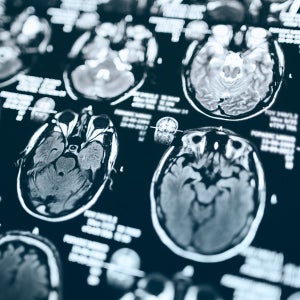

Stroke is the fifth-leading cause of death in the U.S. and the leading cause of long-term disability. But thanks to advances in technology, treatment and prevention, there's more hope than ever for patients who experience a stroke or who are at risk.

When it comes to stroke, time is brain and every second counts. That's why Saint Agnes offers TeleNeurology services, bringing stroke specialists to the bedside through secure, high-speed video technology.

- Review imaging and test results remotely, as needed